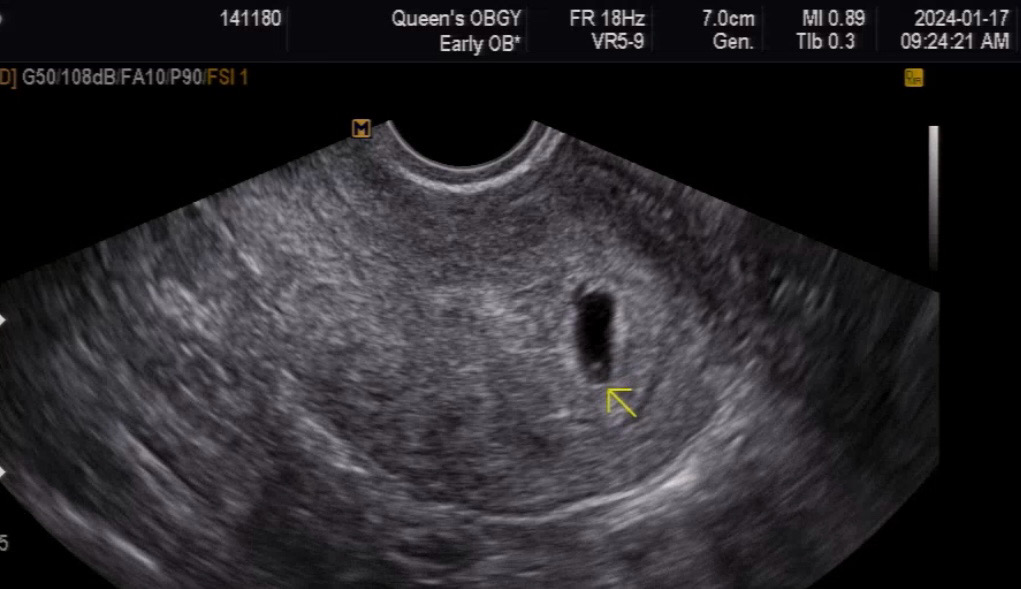

5주 2일차 애기집이랑 난황보고 왔어요💕

병원가기 전까지 얼마나 궁금하고 보고싶었는지.. 시간은 도저히 안가고 기다림의 연속이었는데 드디어 오늘 첫진료를 봤어요. 그동안 아가집 자리는 잘 잡았는지 난황은 있을지.. 아랫배통증 세게 오면 왜구러지??!😳 통증이 없는 날은 왜 없는거지!!!!!😭 유방통증 없으면 왜 없는거지!!!!!😨 말도 많고 걱정도 많았는데 오늘 드디어 병원가서 잘 자리잡고 있는 아가집을 보니까 그동안 묵은 걱정들이 싹 사라졌어요🫣 의사쌤이 보자마자 자궁이 튼튼하다고 해서 더 마음 놓였네요ㅋㅋㅋㅋㅋ 앞으로 9개월!! 잘 지내보자 아가야💜